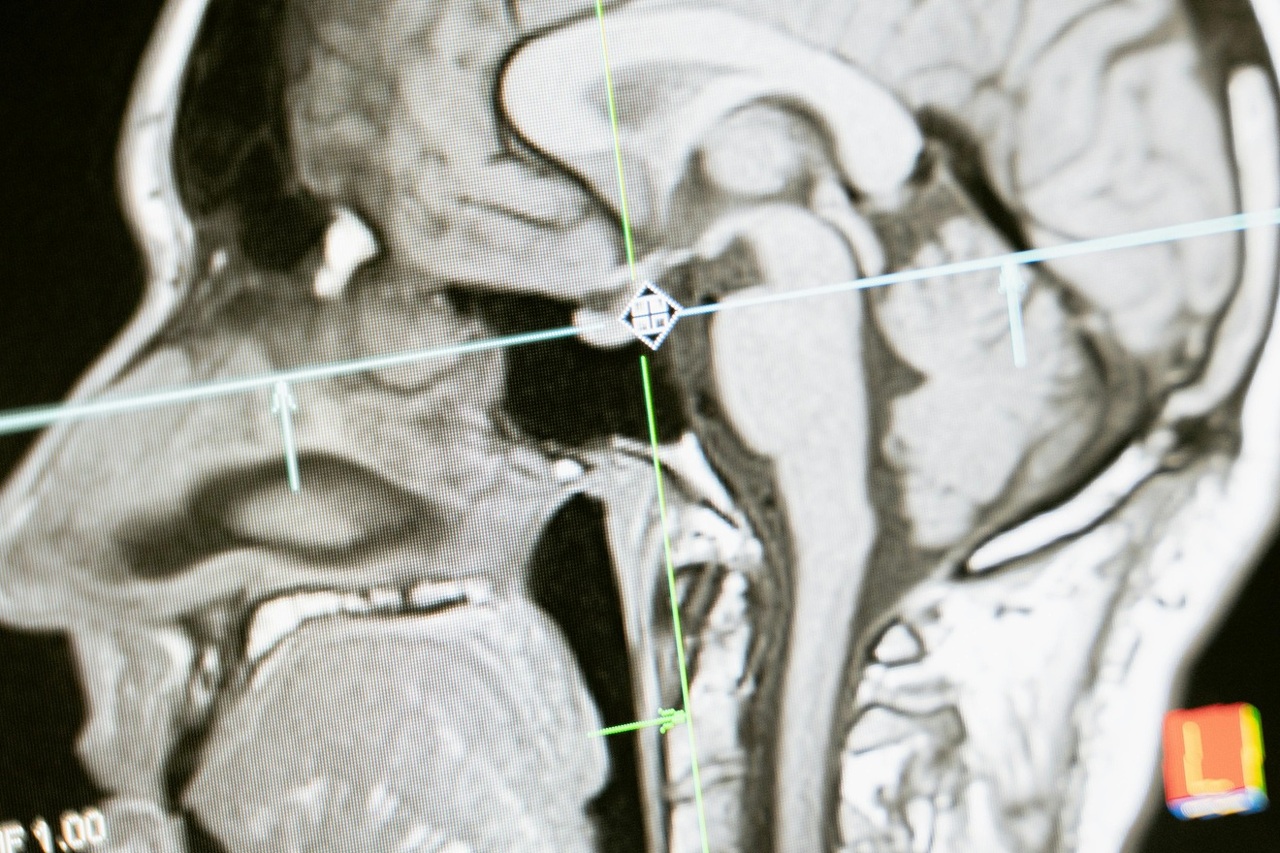

Ovaj proces, iako ključan za razumijevanje kako se u danom trenutku osjećamo, do sada je bio vrlo teško proučavati. „Signali iz unutarnjih organa šire se kroz tijelo, često se preklapaju i teško ih je izolirati i izmjeriti“, naveli su istraživači u službenom priopćenju.

„Senzorni neuroni koji prenose te poruke isprepliću se kroz tkiva – od srca i pluća do želuca i bubrega – bez jasnih anatomskih granica“, dodaju znanstvenici.